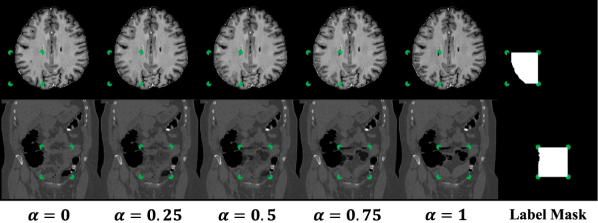

Although and are both normal on their own, the differences between them will cause the interpolation, , to have artificial defects. We train a network to estimate where, and to what degree, a foreign pattern has been introduced. Given as input, the corresponding label includes the patch, , and the interpolation factor, , in the form of pixel-level values (Eqn. 5). The loss is thus a pixel-wise regression if is continuous, or a pixel-wise classification if is discrete. In both cases a standard cross-entropy loss is used (Eqn. 6-7, where represents the model). For continuous , cross-entropy operates on labels that are not one-hot; this is similar to applications such as label smoothing (Szegedy et al. (2016)), network distillation with soft targets (Hinton et al. (2015)), and MixUp augmentations (Zhang et al. (2018)) and has been studied extensively in its own right (Müller et al. (2019); Lukasik et al. (2020)). To obtain predictions during testing, the abnormality score is derived directly from the model’s estimate of the interpolation factor . Examples of and , with varying alpha, are shown in Figure 1. The corresponding label for each example is equal to the label mask scaled by the value.

Note that FPI does not involve any image registration steps. Nevertheless, it is able to create a range of subtle training samples through simple linear interpolation (as seen in Figure 1 and Appendices A and B). We experiment on datasets with varying degrees of alignment, e.g., brain MRI volumes with affine registration and CT data with no alignment (details in Section 3.1). In all cases, FPI is able to form useful training samples that improve detection of outliers.